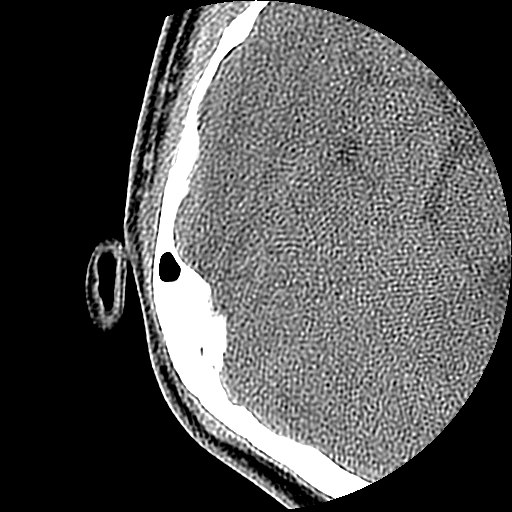

以下是引用随光逐影在2009-8-19 7:25:00的发言:[br]右侧慢性中耳乳突炎,右侧中耳腔及外耳道肉芽肿或胆脂瘤形成。